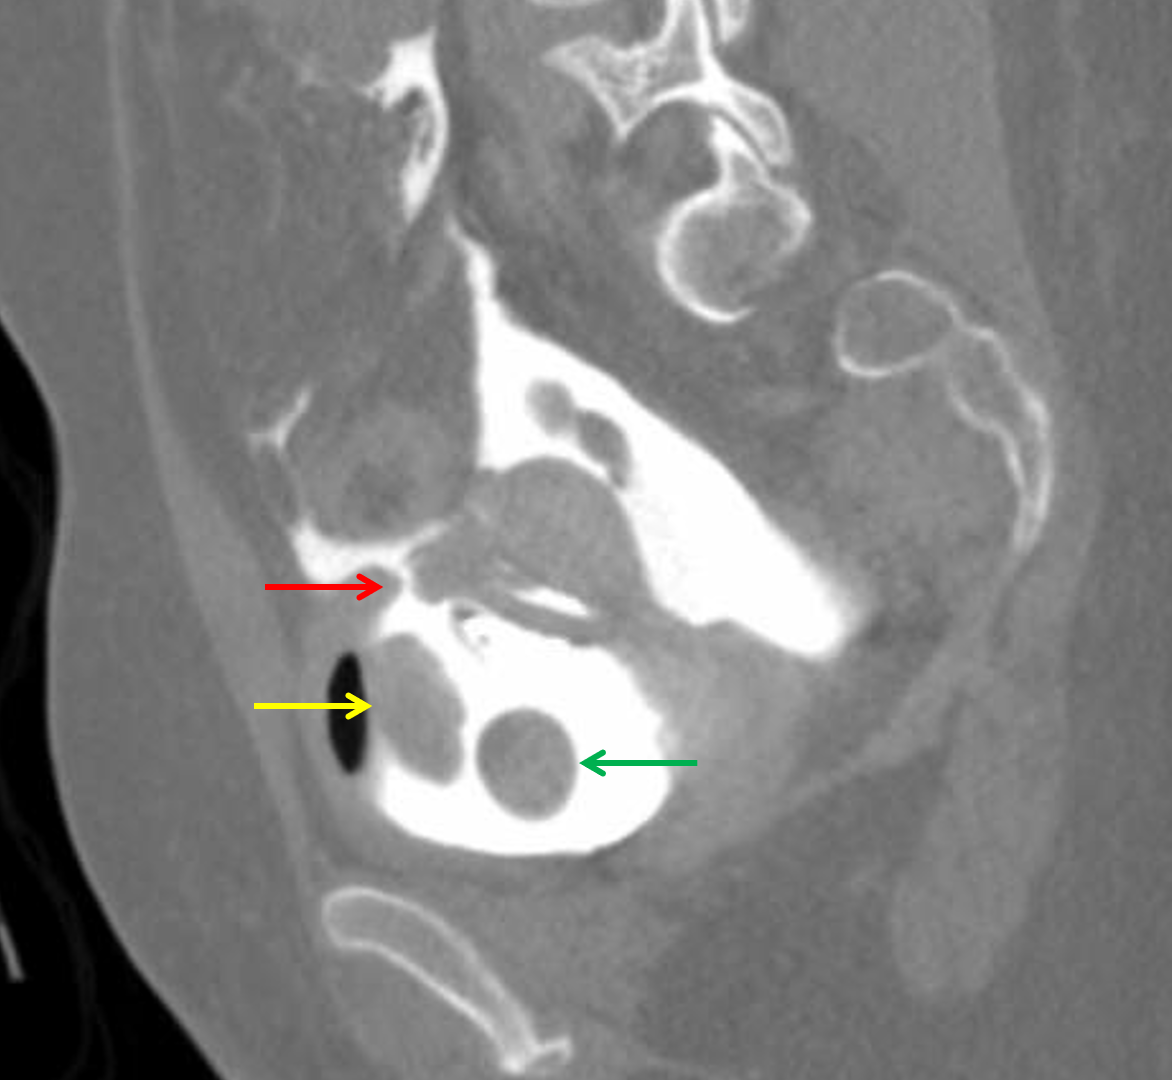

LearningRadiology Bladder Rupture, Intraperitoneal and Extraperitoneal

From www.learningradiology.com

LearningRadiology Bladder Rupture, Intraperitoneal and Extraperitoneal Can A Ruptured Bladder Be Fixed — complicated extraperitoneal bladder ruptures, such as those associated with bone fragments within the. — bladder rupture is a medical emergency that requires prompt treatment. — in general, intraperitoneal bladder ruptures do not heal on their own, so urine continues to bathe the peritoneal cavity until the injury is fixed. The bladder is a mighty strong organ. Can A Ruptured Bladder Be Fixed.